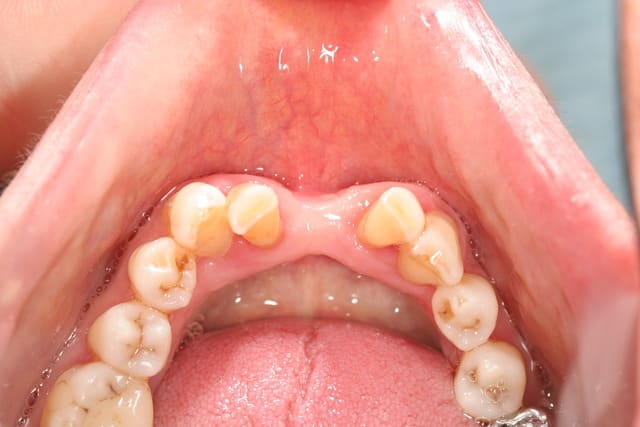

et ici ?? vous feriez quoi ?

32 et 42 pas mobiles

malheureusement, l'espace est réduit pour mettre deux implants.

comment avez vous déjà géré ce type de cas ??

le haut est déjà traité...